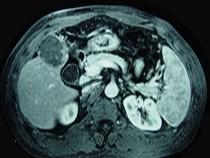

问题 男性,60岁,右上腹胀不适,右肝区叩击痛,影像检查如图,最可能的诊断是()

选项 A.肝硬化 B.肝硬化、外生性肝癌 C.肝硬化、腹腔间质瘤 D.肝硬化、膈下脓肿 E.肝硬化、结节性增生

答案 B